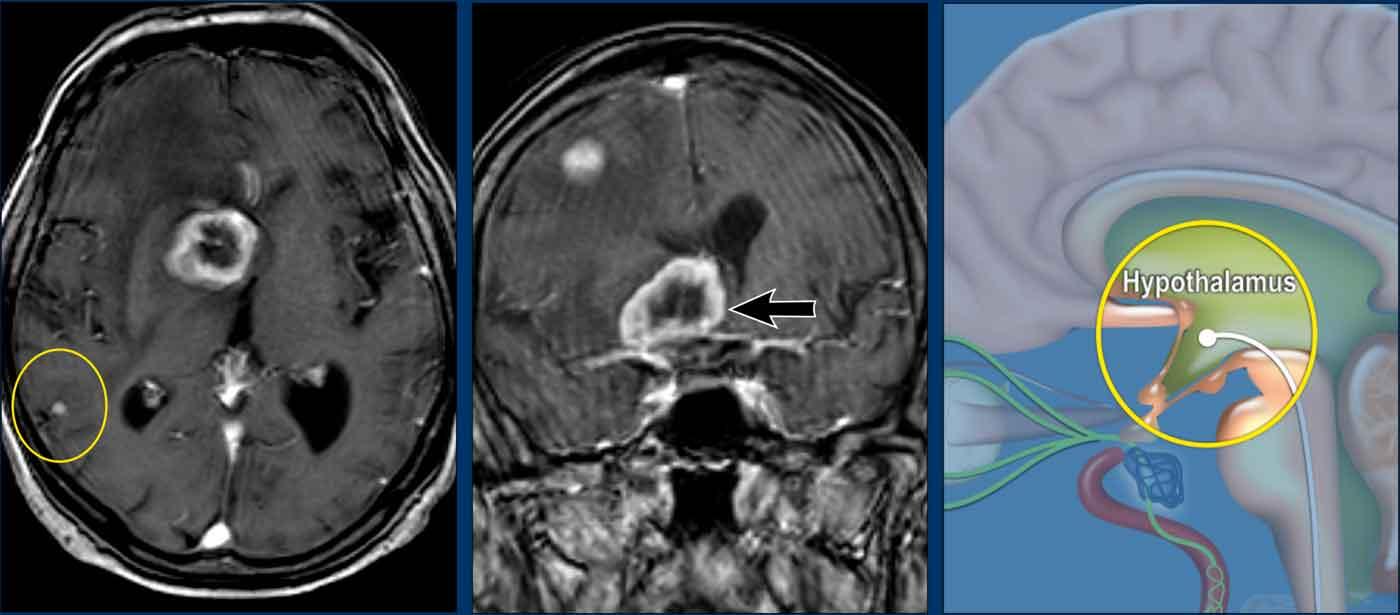

Những hình ảnh này của một phụ nữ 58 tuổi với các triệu chứng thần kinh không đặc hiệu kéo dài nhiều năm, được điều trị bởi bác sĩ phục hồi chức năng.

Hình ảnh

FLAIR 3D trục ngang với ức chế mỡ cho thấy nhiều tổn thương tăng tín hiệu T2 dưới lều tiểu não ở hành tủy bên trái và bán cầu tiểu não hai bên.

FLAIR 3D mặt phẳng vành với ức chế mỡ cho thấy các tổn thương chất trắng hợp lưu quanh não thất và dưới lều tiểu não.

Continue with the next images…

MRI cột sống cổ và cột sống ngực cho thấy nhiều tổn thương trong tủy.

Hình ảnh FLAIR 3D mặt phẳng đứng dọc cho thấy nhiều ngón Dawson hợp lưu và hình ảnh FLAIR 3D mặt phẳng trục ngang cho thấy nhiều tổn thương T2 ở thân não.

Conclusion

Radiological consistent with Multiple Sclerosis.